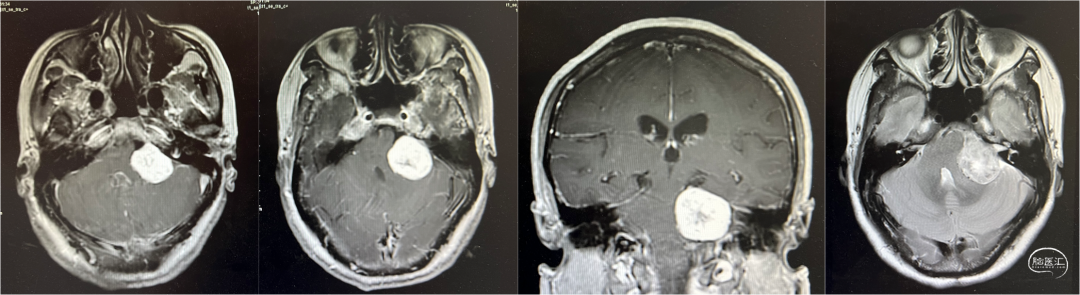

临近文山州庆假期前夕,由消化内科转诊,丘北县人民医院神经外科接诊了一例富血供的颅底脑干肿瘤患者。该患者有多年的头疼病史,本次住院,经头颅磁共振检查,发现了颅底、脑干区的巨大占位,脑干已明显受压变形,亟需手术治疗,并且强烈希望能够在丘北本地接受手术。

因疾病复杂,手术难度高,华山医院援滇医疗队冯睿博士组织了科内讨论,李啟能主任组织了全院的多学科讨论,以充分评估在县医院手术的可行性。拟进行充分术前准备(包括全脑DSA)后,在州庆假期结束后进行手术。

患者术后在手术室内即复苏、恢复神志,气管插管保留至次日拔除。患者术后第三日开始下床活动,并开始接受床旁康复治疗。磁共振复查提示,肿瘤全切除,脑干无缺血表现。